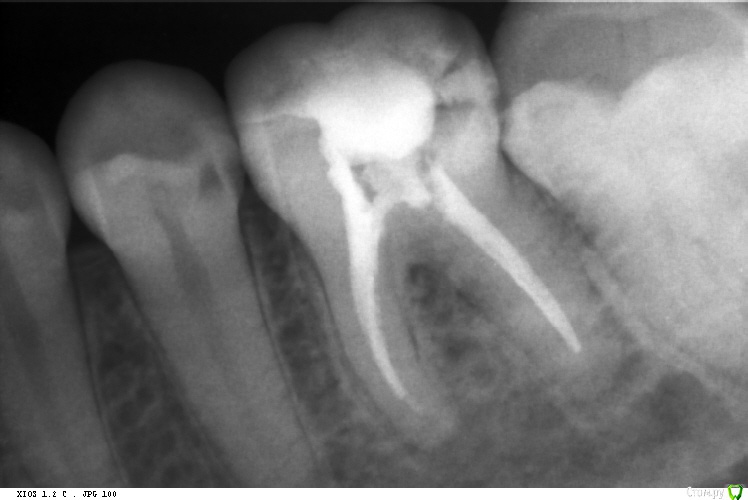

St. Опубликовано 23 марта, 2016 Автор Поделиться Опубликовано 23 марта, 2016 Эх, что-то сезон косяков. Аж руки опускаются... Видимо пора в отпуск. 36 пульпит. Запаковала по апексу -0,5. Что получилось - снимок 2. Попросили перепаковать. В итоге по апексу в 0, плюс 1,5 часа времени 1 Ссылка на комментарий